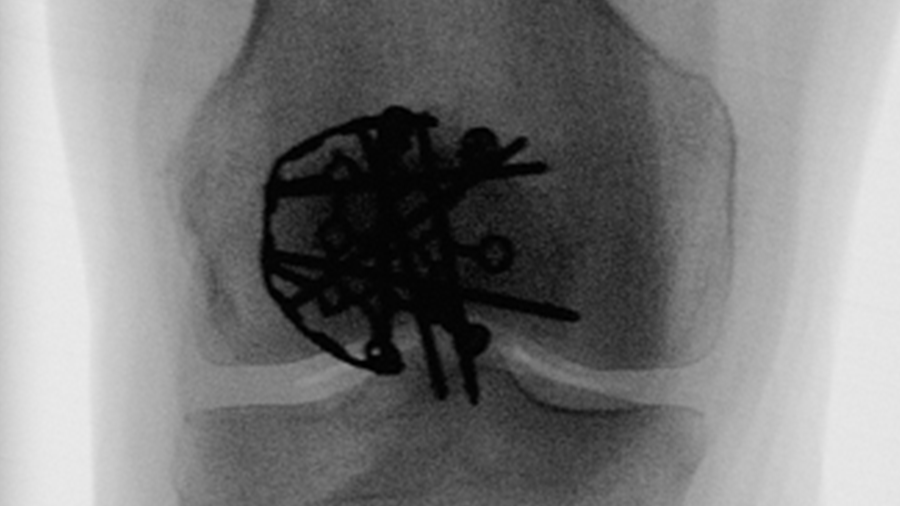

Veterinary Screw Targeting Clamp (STC)

The new Veterinary Screw Targeting Clamp (STC) becomes a valuable addition to equine healthcare. Originally developed by the AO Technical Commission's Foot and Ankle Expert Group, the STC was reinforced and enriched for the use in large animal.

The STC is designed to provide the ability to maintain compression and targeted screw insertion. Improved accuracy of screw insertion gives more consistent and confident fracture repair and allows precise placement of specific screws into subchondral bone cysts close to joint space.